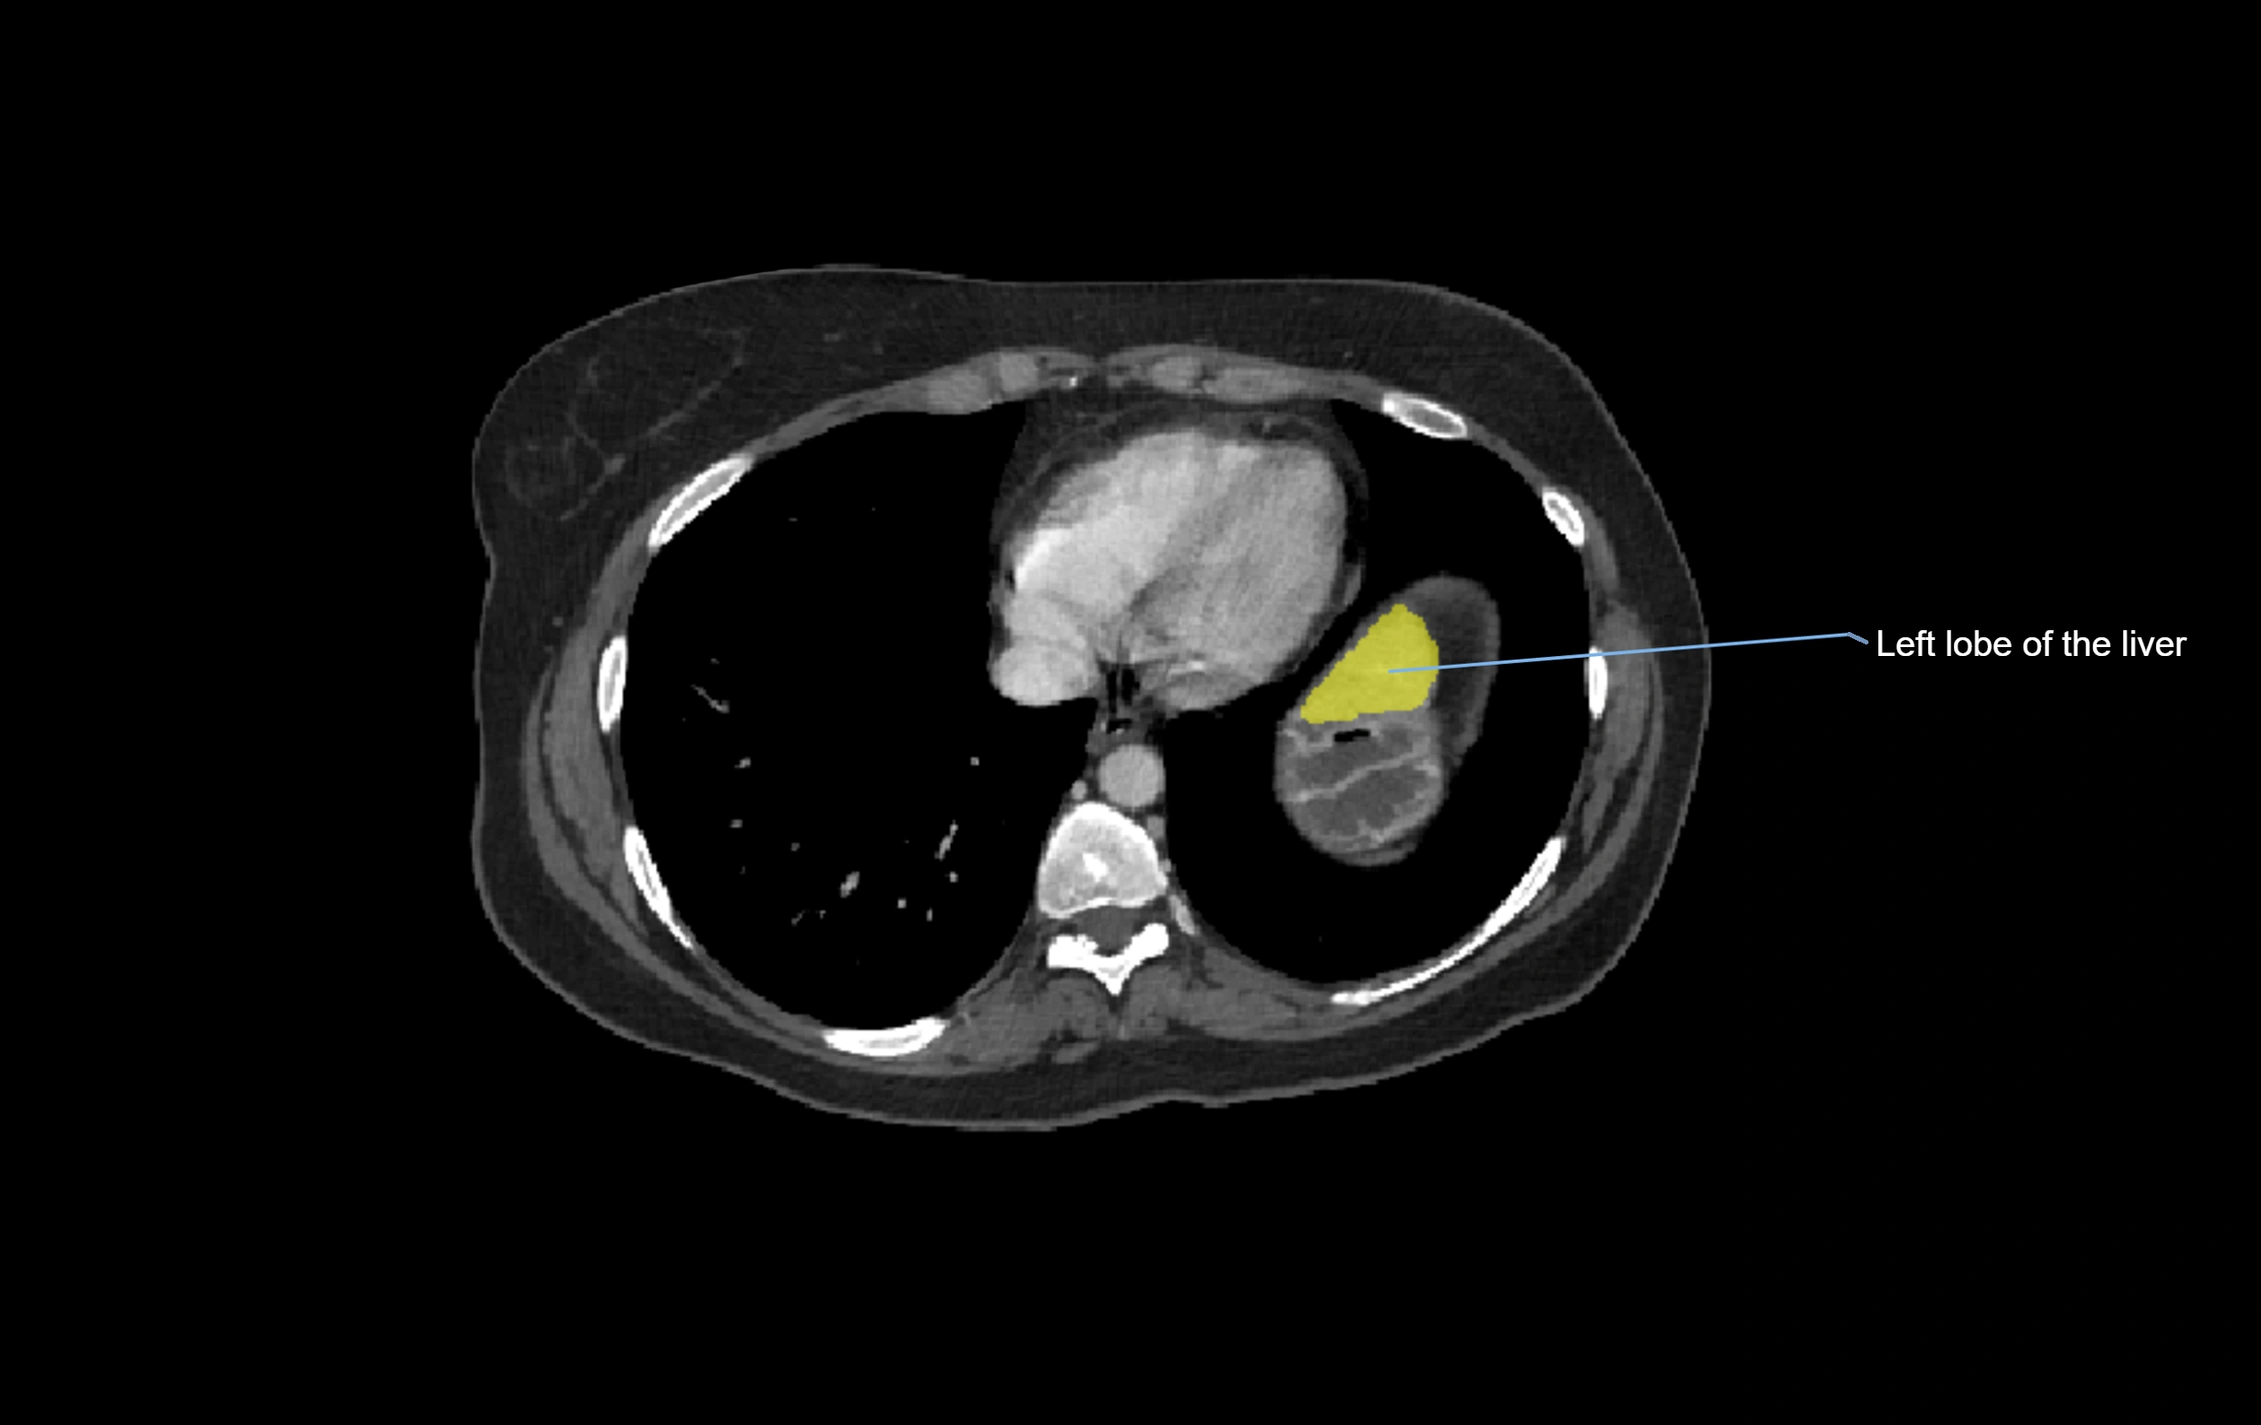

MRI image

image